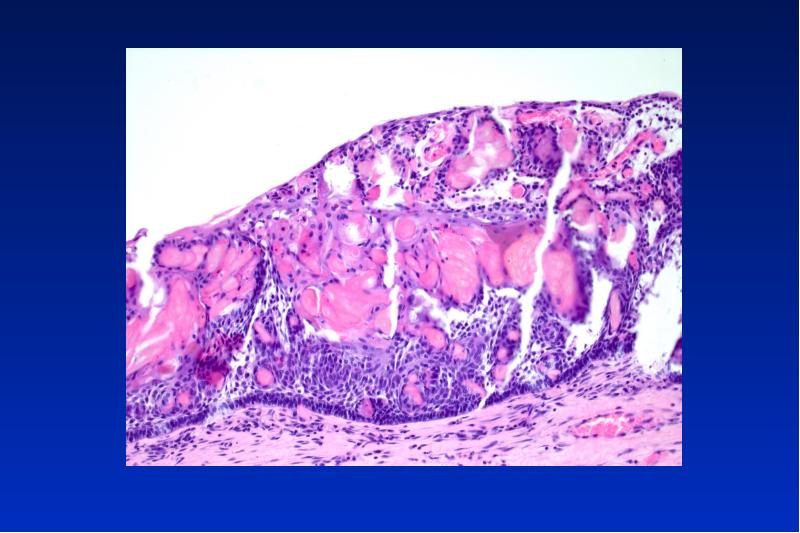

- 4. Radikuläre Zyste Ät: Entzündung Lok: OK, Frontalregion Alter: 30-40

- 5. Pathogenese der radikulären Zyste Karies ----> Pulpitis --->